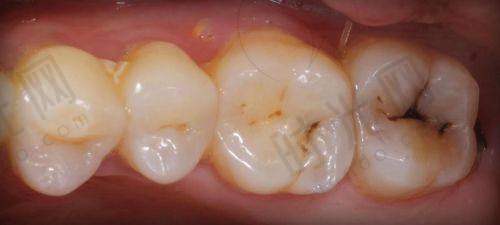

补牙拔牙及其他牙齿治疗相关费用也特别清晰。超声波洁牙180元起,能有效清洁牙齿;根管治疗580元/根起,解决牙齿疼痛问题;进口树脂补牙380 - 1080元/颗起,修复牙齿的外形和功能。

真相:种牙收费高并不一定就代表适合自己。不同的种植体品牌和医生技术对应不同的价格,患者应该根据自己的口腔情况和经济实力来选择。例如,对于单颗牙齿缺失的患者,如果口腔条件较好,选择价格相对较低的韩国登腾种植牙也能达到不错的成效,不一定非要选择价格高的瑞典诺贝尔种植牙。